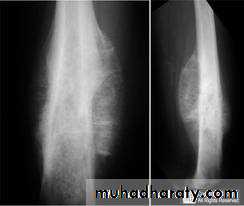

4.Periosteal reaction

the causes of localized peiosteal reactions adjacent to a lytic or sclerotic lesions are :

.Osteomyelitis.Malignant bone tumour , particularly Ewing sarcoma & osteosarcoma

.Occasionally metastasis , particularly neuroblastoma

.Langerhans histiocytosis

.Trauma

Ewing sarcoma